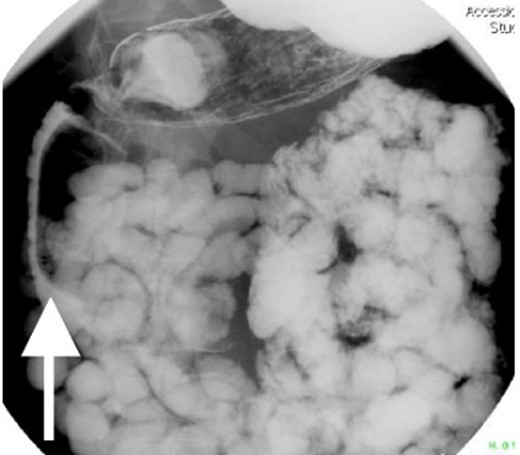

Small bowel series showing duodenal filling defect (posterior view).

Small bowel series showing duodenal filling defect (anterior view).

With regard to diagnostic workup, the literature has described cases with similar results to ours. Small bowel contrast studies frequently show smooth-walled polypoid filling defects within the duodenal bulb, and CT imaging is useful for delineation of adjacent structures including the common duct and pancreas [1]. Moreover, similar to the pathological results found in our patient, upper endoscopy biopsies are often equivocal as they are submucosal-based lesions [1]. The most useful diagnostic study, however, is endoscopic ultrasound, which may help distinguish the consistency and bowel layer of origin [2, 6], which unfortunately was not available at our institution.